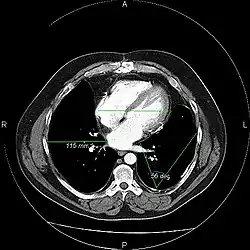

A picture archiving and communication system (PACS) is a medical imaging technology which provides economical storage and convenient access to images from multiple modalities (source machine types).[1] Electronic images and reports are transmitted digitally via PACS; this eliminates the need to manually file, retrieve, or transport film jackets, the folders used to store and protect X-ray film. The universal format for PACS image storage and transfer is DICOM (Digital Imaging and Communications in Medicine). Non-image data, such as scanned documents, may be incorporated using consumer industry standard formats like PDF (Portable Document Format), once encapsulated in DICOM. A PACS consists of four major components: The imaging modalities such as X-ray plain film (PF), computed tomography (CT) and magnetic resonance imaging (MRI), a secured network for the transmission of patient information, workstations for interpreting and reviewing images, and archives for the storage and retrieval of images and reports. Combined with available and emerging web technology, PACS has the ability to deliver timely and efficient access to images, interpretations, and related data. PACS reduces the physical and time barriers associated with traditional film-based image retrieval, distribution, and display.

Most PACS handle images from various medical imaging instruments, including ultrasound (US), magnetic resonance (MR), Nuclear Medicine imaging, positron emission tomography (PET), computed tomography (CT), endoscopy (ES), mammograms (MG), digital radiography (DR), phosphor plate radiography, Visible Light Photography (VL), Histopathology, ophthalmology, etc. Additional types of image formats are always being added. Clinical areas beyond radiology; cardiology, oncology, gastroenterology, and even the laboratory are creating medical images that can be incorporated into PACS. (see DICOM Application areas).

Typically a PACS consists of a multitude of devices. The first step in typical PACS systems is the modality. Modalities are typically computed tomography (CT), ultrasound, nuclear medicine, positron emission tomography (PET), and magnetic resonance imaging (MRI). Depending on the facility's workflow most modalities send to a quality assurance (QA) workstation or sometimes called a PACS gateway. The QA workstation is a checkpoint to make sure patient demographics are correct as well as other important attributes of a study. If the study information is correct the images are passed to the archive for storage. The central storage device (archive) stores images and in some cases reports, measurements and other information that resides with the images. The next step in the PACS workflow is the reading workstations. The reading workstation is where the radiologist reviews the patient's study and formulates their diagnosis. Normally tied to the reading workstation is a reporting package that assists the radiologist with dictating the final report. Reporting software is optional and there are various ways in which doctors prefer to dictate their report. Ancillary to the workflow mentioned, there is normally CD/DVD authoring software used to burn patient studies for distribution to patients or referring physicians. The diagram above shows a typical workflow in most imaging centers and hospitals. Note that this section does not cover integration to a Radiology Information System, Hospital Information System and other such front-end system that relates to the PACS workflow.